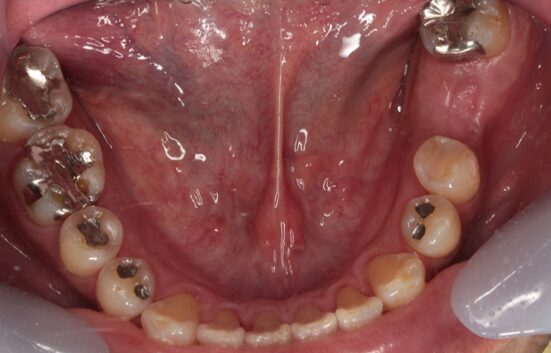

32歳女性